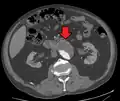

Abdominal aortic endoprosthesis, CT scan, original aneurysm marked in blue